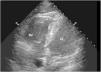

An 88-year-old male developed hypoxia, tachycardia, mild fever, agitation and confusion few hours after undergoing hip joint hemiarthroplasty. Bedside point of care ultrasound revealed dilated right atrium and right ventricle (RV) but normal dimensions and function of left ventricle (LV). RV free wall was severely hypokinetic except for the RV apex which was hyperkinetic (Fig. 1, Video 1: apical 4 chamber view). This preserved apical contractility of RV with severe hypokinesia of rest of the RV free wall is known as McConnell's sign (Video 2: RV apex in red circle), commonly observed in patients with acute pulmonary thromboembolism (PTE). In contrast, global hypokinesia is observed in chronic RV dysfunction. No evidence of PTE but bilateral subtle ground glass opacities and interstitial septal thickening was seen on CT of chest (Fig. 2). A diagnosis of Fat Embolism Syndrome (FES) was made and patient recovered with supportive care.